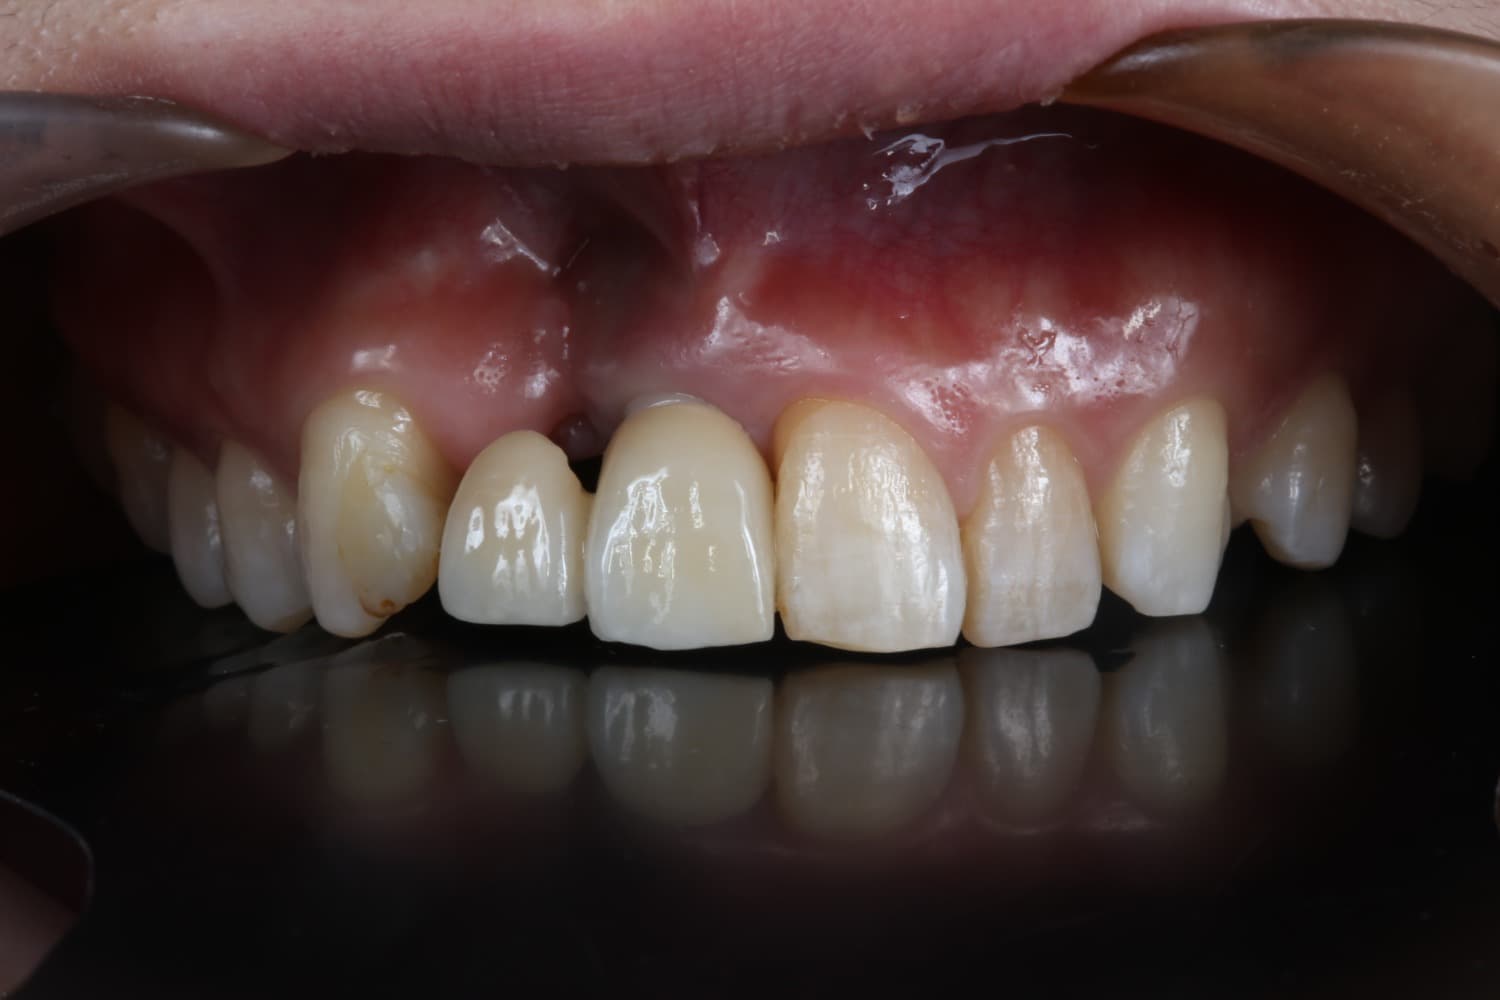

左上1のインプラント治療

Before

After

保存不可能な左上1を抜歯して、インプラント治療を行った 今回は歯間乳頭を作るために部分矯正も行う GBRやCTGも含む

年齢

30代

性別

女性

主訴

前歯が長くなってきた

治療期間

2年

治療回数

20回

費用

120万円

副作用・リスク

腫脹、疼痛